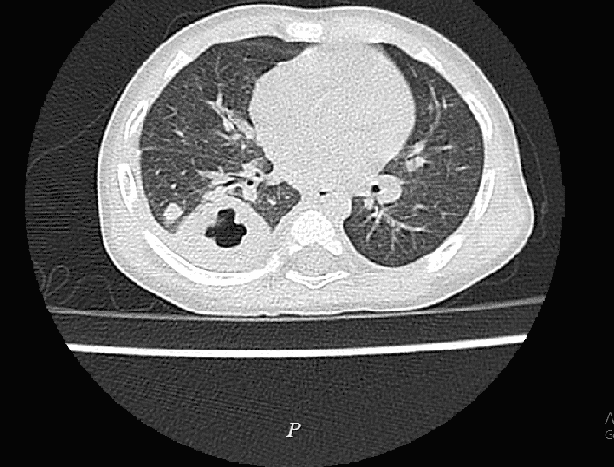

Thông tin từ Bệnh viện Đa khoa Hùng Vương ngày 19/8 cho biết sau khi tiếp nhận, đến ngày thứ 5 điều trị, bệnh nhi vẫn còn sốt cao từng cơn 40 độ, trong cơn sốt bị rét run, ho đờm nhiều, khò khè. Nhận thấy đây là tình trạng nặng, các bác sĩ Khoa Nhi đã cho trẻ làm các xét nghiệm máu, chụp XQuang tim phổi, cấy máu, chụp cắt lớp vi tính phổi.

Kết quả kiểm tra cho thấy bệnh nhi bị nhiễm khuẩn huyết, áp xe phổi. Ba ngày sau, kết quả cấy máu cho thấy bé dương tính với Whitmore (Burkholderia pseudomallei).